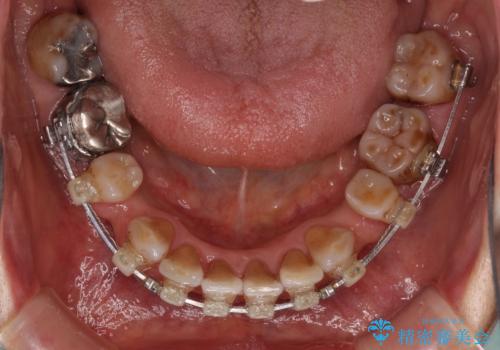

- 矯正装置

- クリアブラケット

- 2年7ヶ月

- 突出した口元を引っ込めることを希望して来院された患者様です。

上下左右第一小臼歯4本を抜歯して、口元を改善するワイヤー矯正を行うこととしました。